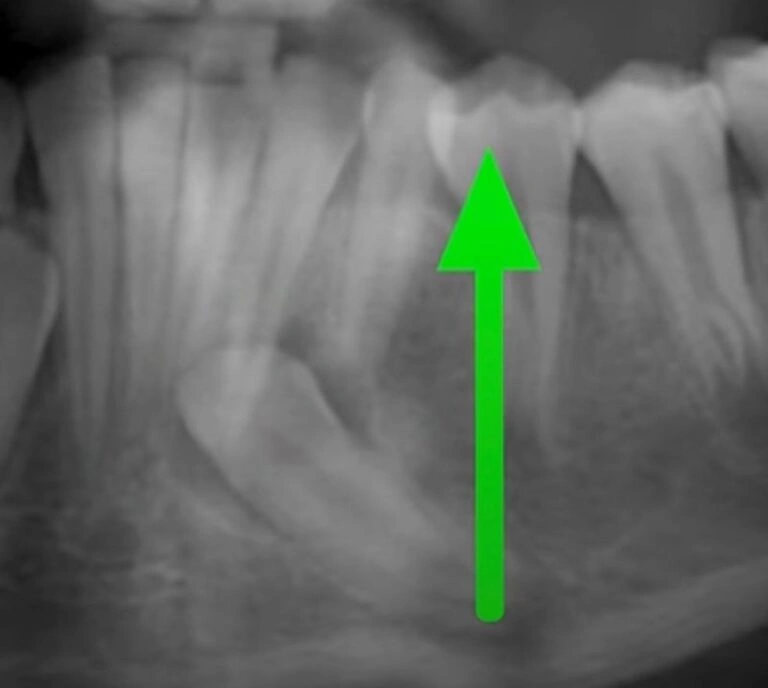

1. No Adult Tooth Yet

Sometimes, the adult tooth that’s supposed to push out the baby tooth just hasn’t formed yet or isn’t ready to come in. Occasionally, this delay is due to genetics, and some kids may experience late tooth eruptions. I’ve had cases where kids haven’t had their adult front teeth come in until they’re 10! (Like Luciano’s case below!)

While it’s rare, it’s good to keep in mind that patience might be the only solution.